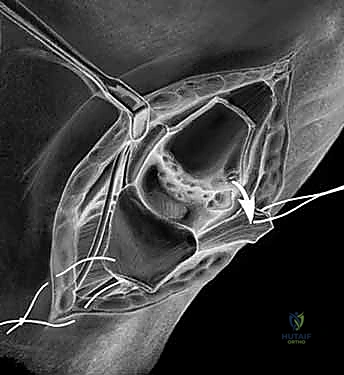

1. استئصال العظم المربعي مع إعادة بناء الأربطة (Trapeziectomy with LRTI)

تُعد هذه العملية "المعيار الذهبي" (Gold Standard) والأكثر شيوعاً ونجاحاً عالمياً لعلاج هذه الحالة.

جراحة استئصال العظم المربعي وإعادة بناء الأربطة LRTI

• آلية العملية: يقوم الجراح بإزالة "العظم المربعي" (Trapezium) بالكامل، وهو العظم الذي يسبب الاحتكاك المؤلم. بمجرد إزالته، يختفي الألم تماماً لأنه لم يعد هناك عظم يحتك بعظم.

• **إعادة بناء الأربطة (LRTI):